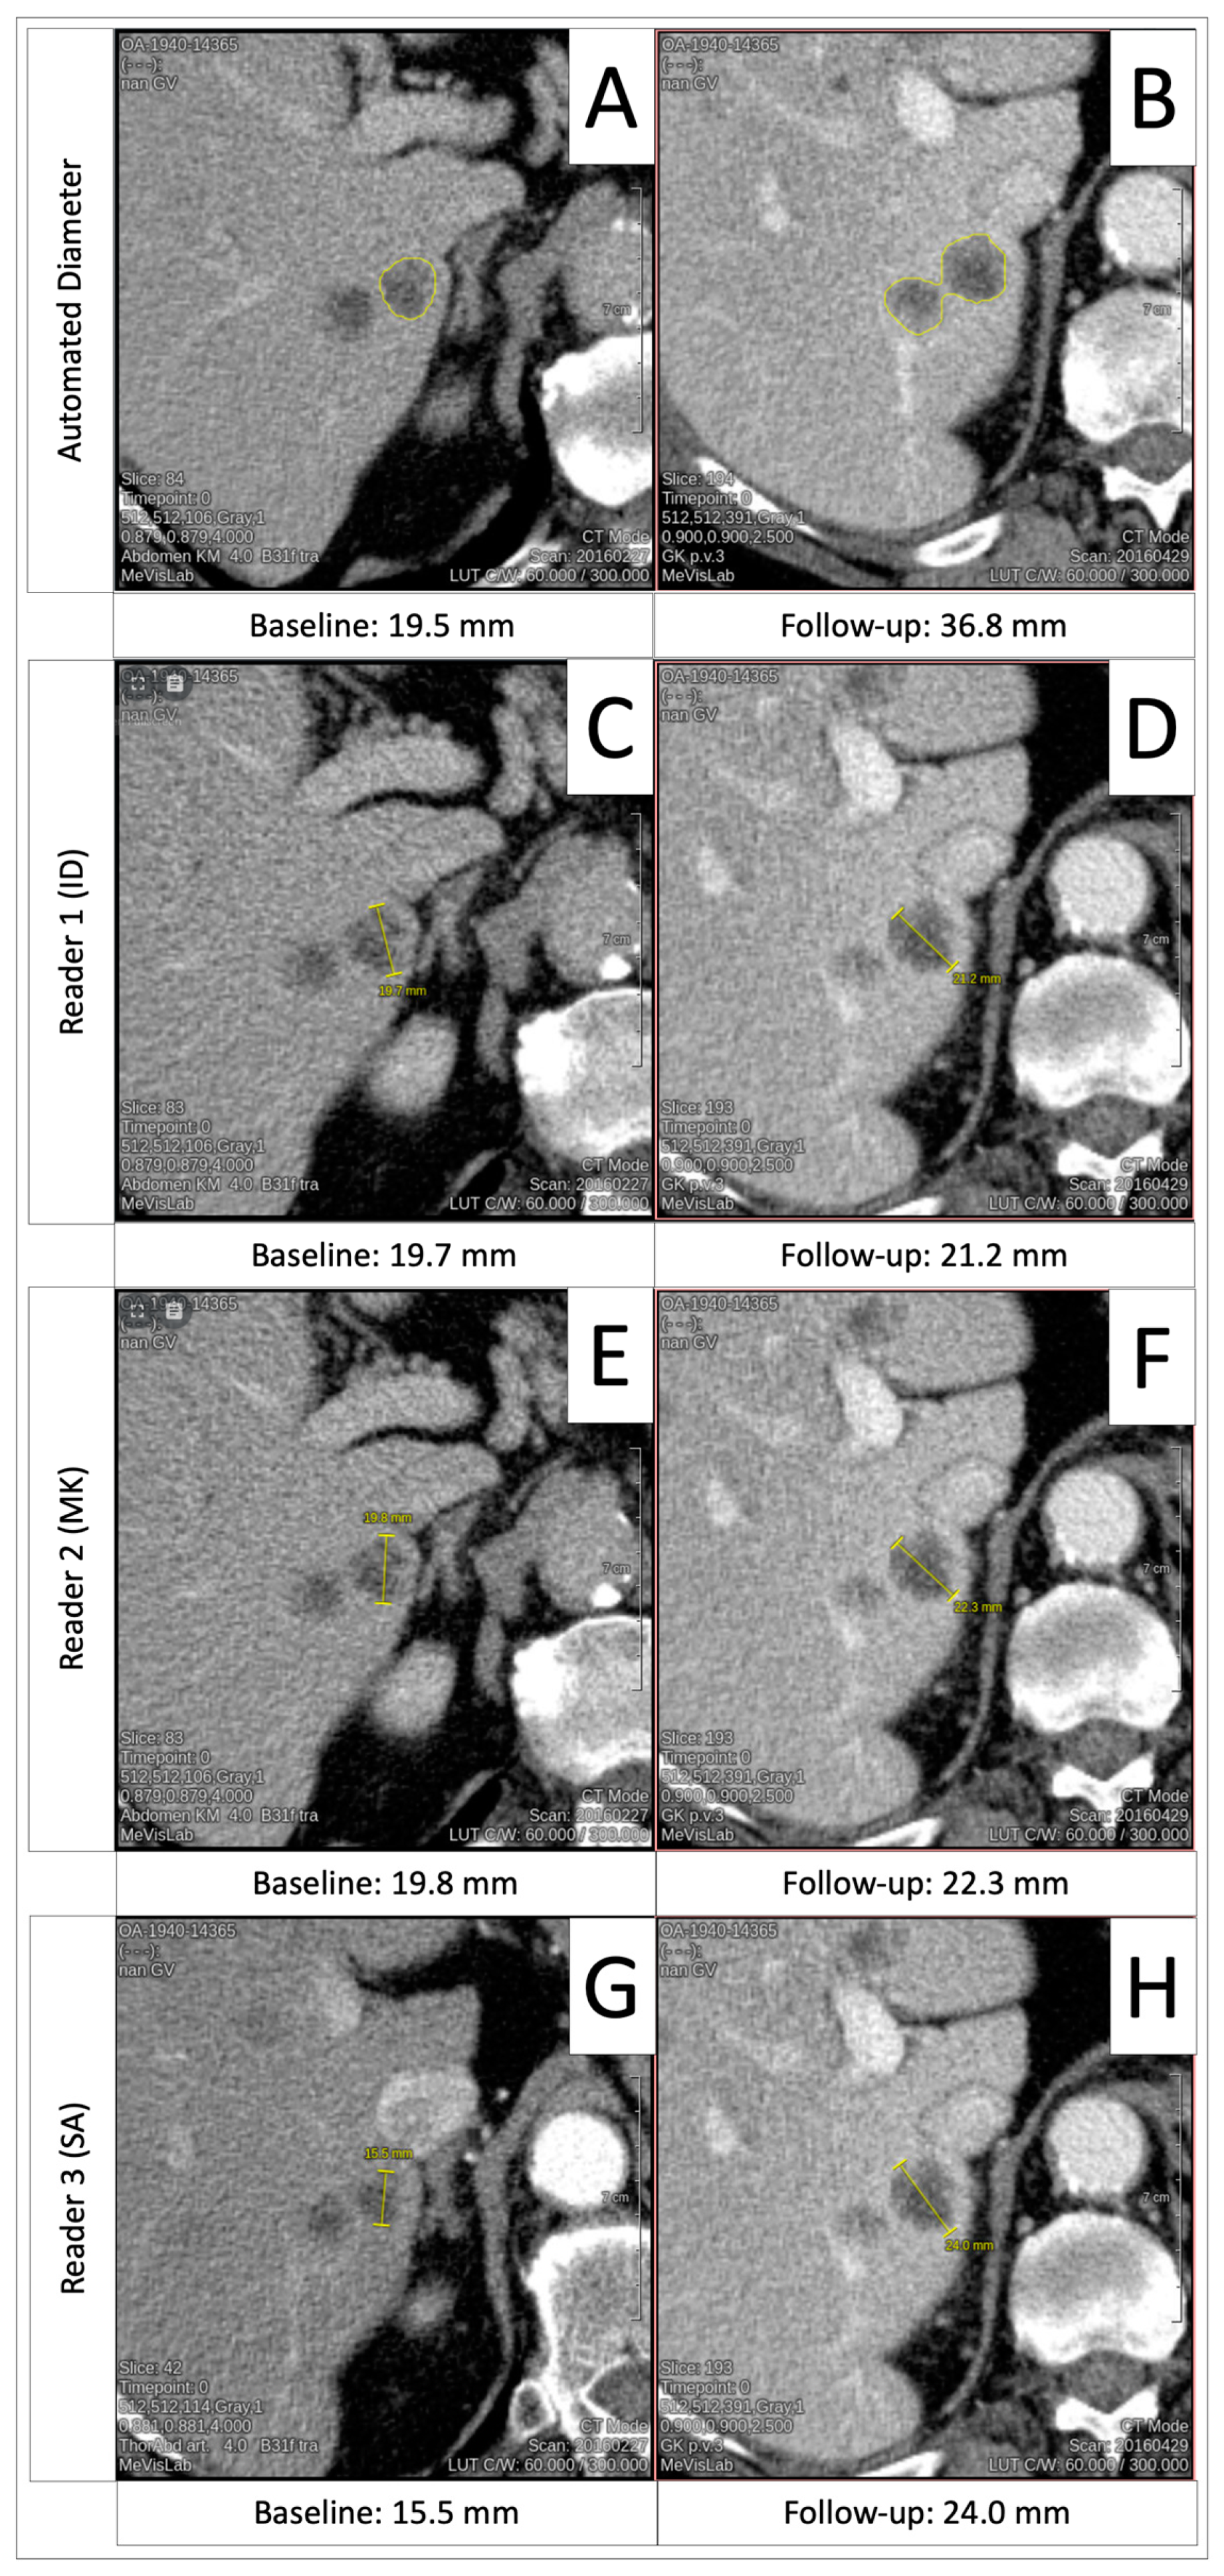

3.6. Progressive Disease Timepoint Response Deviation